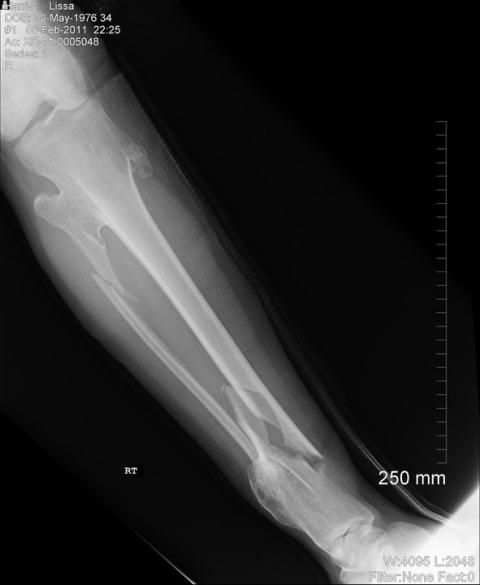

Thanks for your patience this week. I'm back on the job as of today, posting news from around the Catskills, and Lissa will be back online helping me on Monday. (Yup, that's her leg, post-break, in the x-ray above.) We return to Watershed Post HQ in Andes today, after a week of hospitals, shuttling around to doctors appointments, and lots of exotic pain medications.

Lissa is currently sporting an amazing contraption called an "external fixator." (Click here to see an example, but only if you have a strong stomach.) It's a cyborg-like device on her right ankle, and will have another surgery in two weeks to implant an internal solution into her leg. But her doctor says no damage has been done, so we're on our way back to normal.